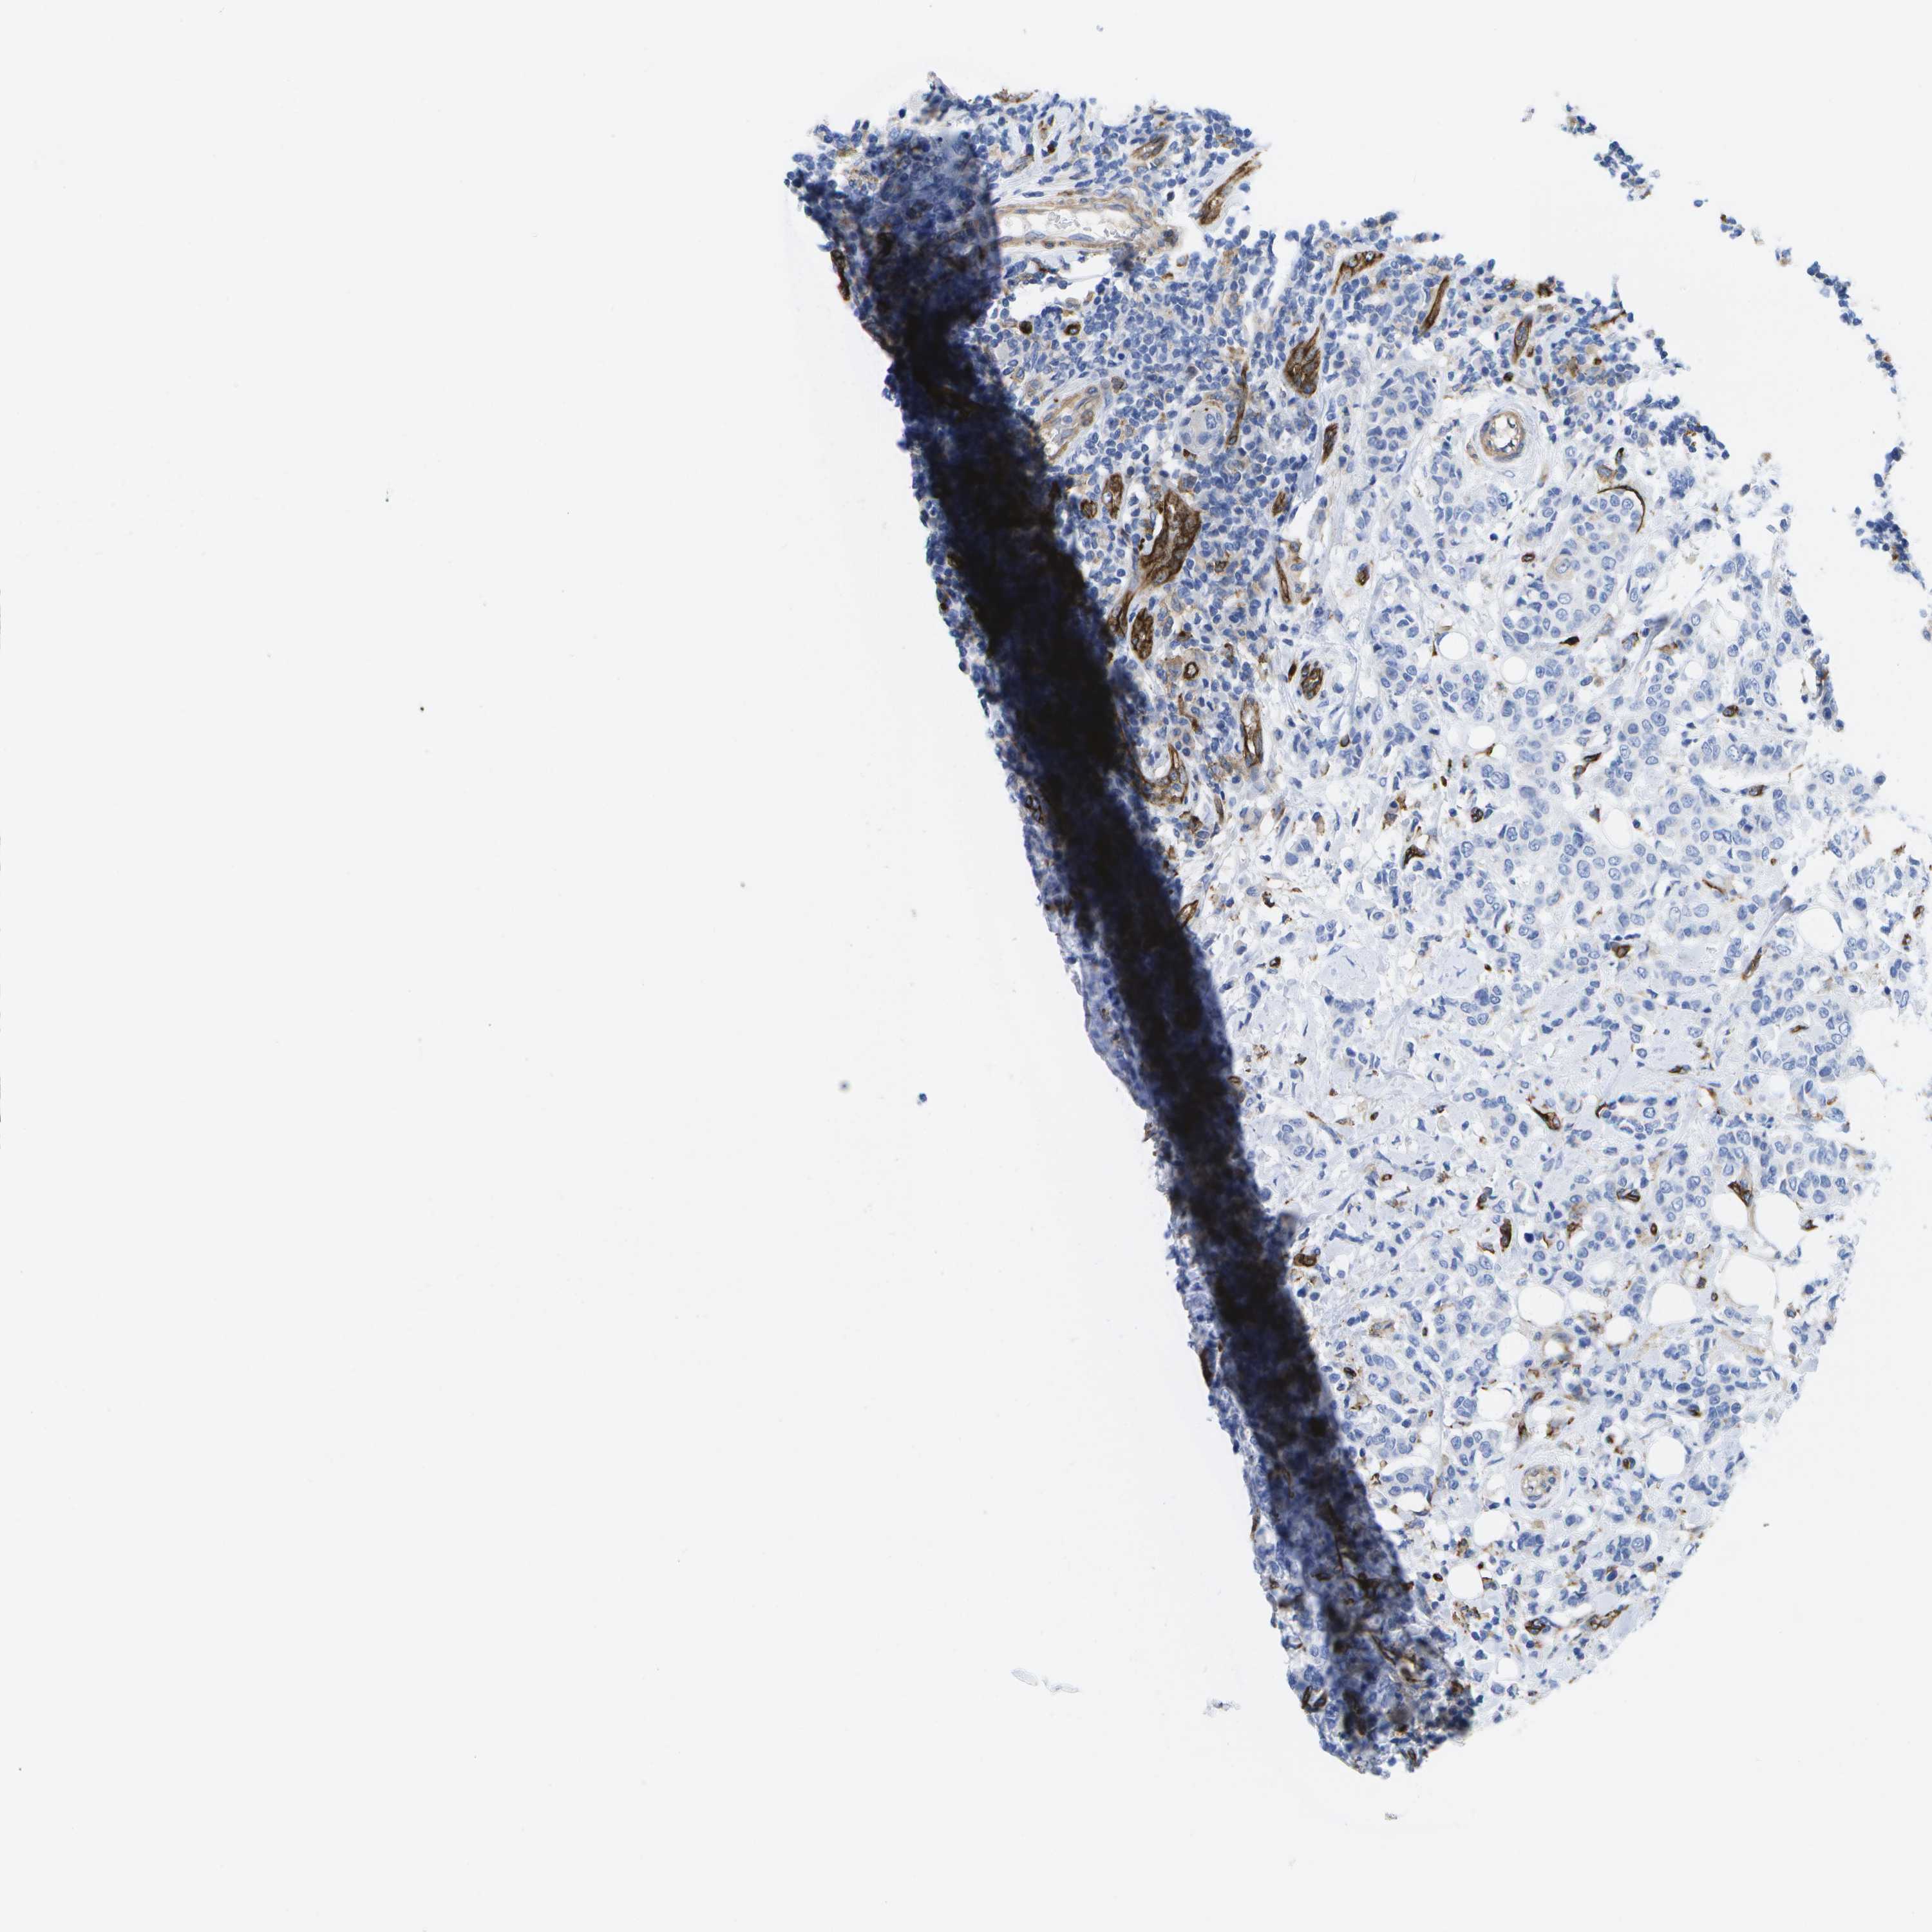

CANCER BREAST CANCER Show tissue menu

BRCA TCGA BRCA VALIDATION PROTEIN EXPRESSION